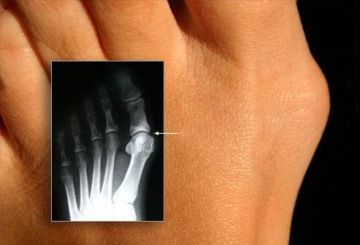

VYBOČENÝ PALEC – HALLUX VALGUS

Při používání nevhodné obuvi a nestejné délce dolních končetin je pohyb svalů a tah šlach v chodidle nerovnoměrně rozložen a tím mohou být způsobeny deformace kosterní části nohy.

Nejčastější defekt chodidla je vybočení palce – Hallux Valgus.

Vybočení palce způsobuje také nesprávná obuv s vysokými podpatky.

Při deformacích vznikají na kloubech otlaky a na plošce nohy se mohou tvořit mozoly.

Řešením pro vybočený palec je napravení nestejné délky končetin, pravidelné cvičení a masírování (uvolňování) chodidla a používání korekčních pomůcek. Dalším řešením je chirurgický zásah, který ovšem neřeší příčinu tohoto defektu ale pouze následek.